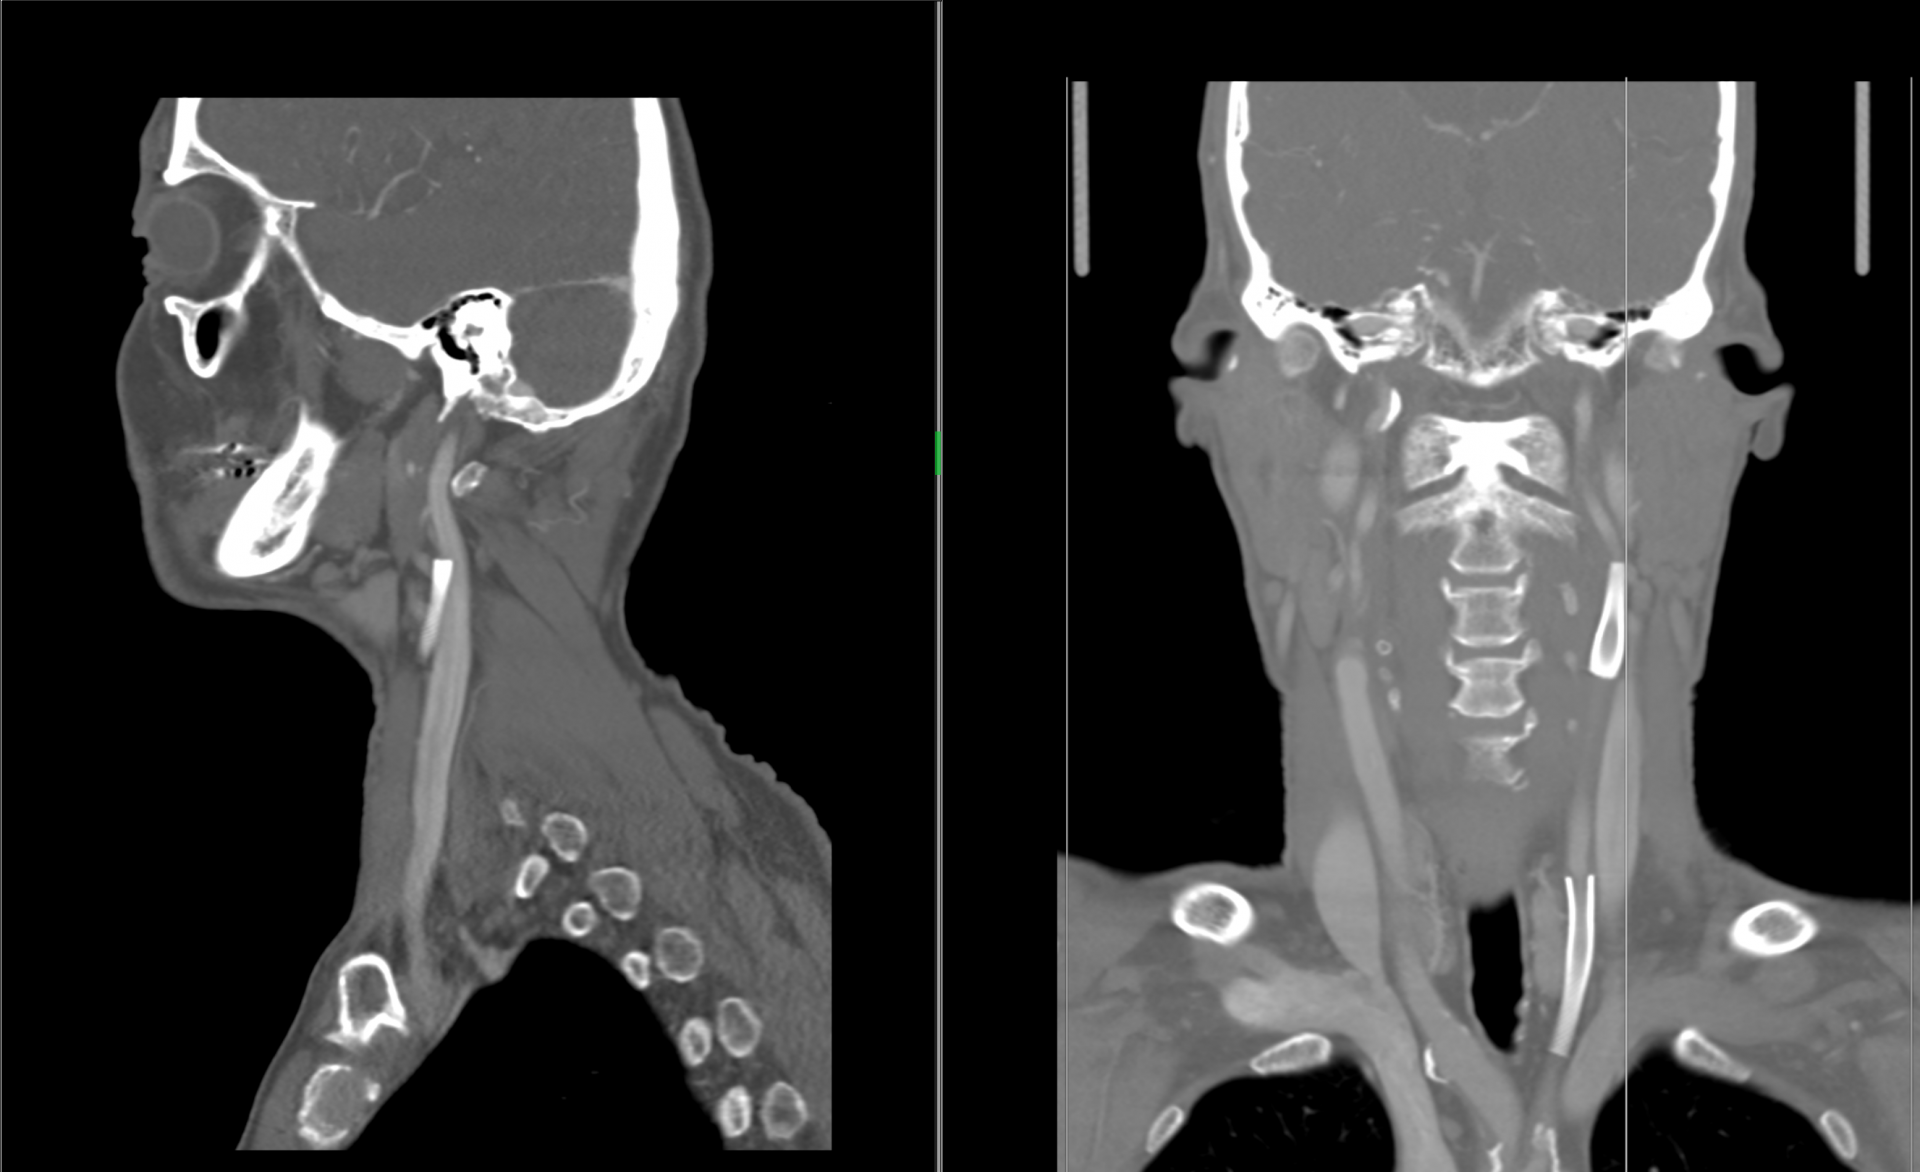

Ukázky snímků